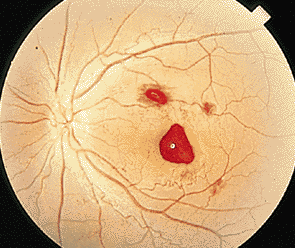

對于很多患者而言,玻璃體變性主要原因就是隨著年齡不斷增加,新陳代謝不斷變緩,使得玻璃體自身變性。比如像星狀玻璃體變性,常常見于50歲以上,不過它只是引起視力的不適,并不會導致視力下降。因為玻璃體內新陳代謝緩慢,而出現(xiàn)了含鈣的脂質白色小球。而玻璃體變性中更為嚴重的是出現(xiàn)液化現(xiàn)象,特別是閃輝性玻璃體液化,由于嚴重眼外傷和手術后眼內出血導致的玻璃體或前房會出現(xiàn)無數(shù)黃白色和其他顏色的膽固醇結晶。

對于玻璃體混濁這樣復雜的癥狀,一般的眼科醫(yī)院無法根治,由于眼睛玻璃體的特殊性,目前尚無有玻璃體變性的特效藥,只能經過長期的治療和鞏固,使得玻璃體不會出現(xiàn)其他病變。所以對于病情較為嚴重的玻璃體變性患者而言,就像因為變性引發(fā)的視網膜剝離或玻璃體出血等等,這些會出現(xiàn)視力嚴重減退,眼睛發(fā)紅、疼痛、畏光等等,一定要到專業(yè)的眼科醫(yī)院進行醫(yī)治,比如在廈門眼科醫(yī)院的眼底專科,常年來除了眼底病之外,玻璃體變性治療領域在全國也是處于領先位置。